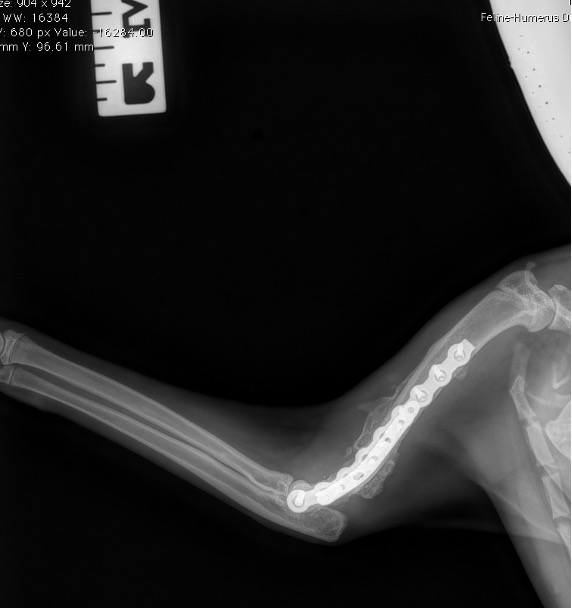

Exemple 3 :

Figure 9 : Pré-Op

Figure 10 : Opération

Figure 11 : Post-Op Immédiat

Figure 12 : Post-Op 1 mois